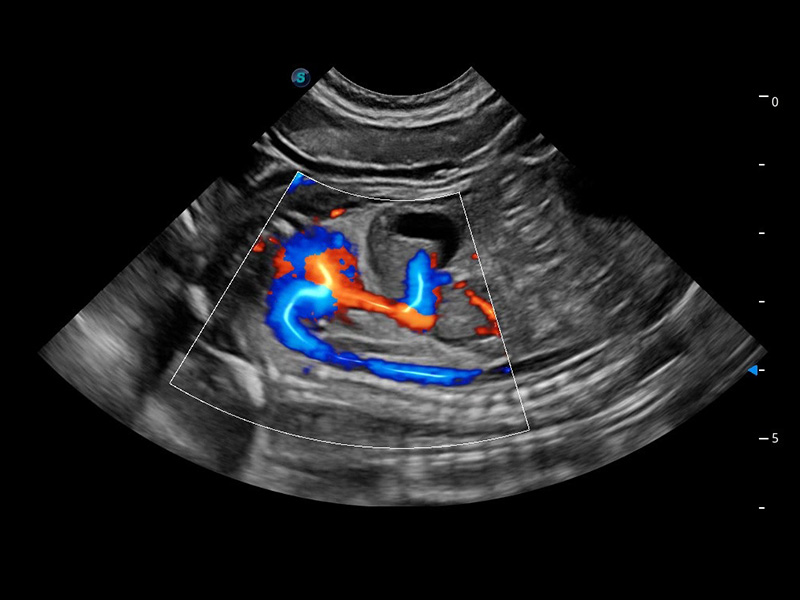

(猫)髂动脉血流频谱

(犬)胆囊泥沙

(猫)膀胱结晶

(犬)肾脏血流